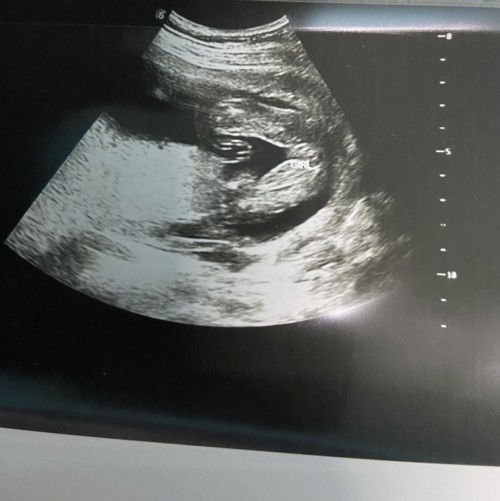

Hye mommy’s.. kalau mcm ni girl ye? Tanya saja2 sbb dr xcomfirm lagi just assume girl dulu. Tq yg sudi komen

Nampak mcm girl 😍